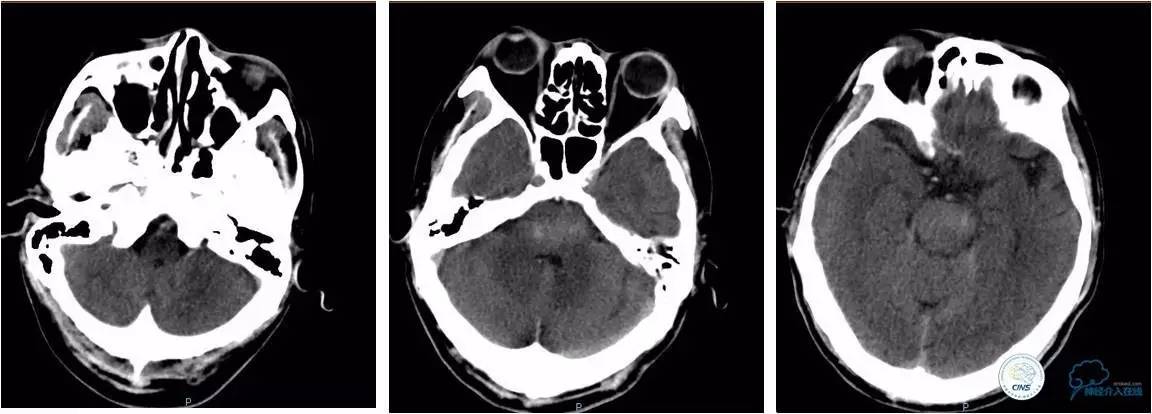

★术后24小时、术后4天、术后14天复查头颅CT。

》术后情况

★术后带气管插管入ICU;

★持续替罗非班泵入24小时后改拜阿司匹林100 mg、波立维75 mg胃管内注入;

★术后十天拔除气管插管,神志转清,呼之眼球能活动,四肢无自主活动,呈闭锁状态;

★术后三周转至康复科康复锻炼;

★三个月mRs评分:5分。